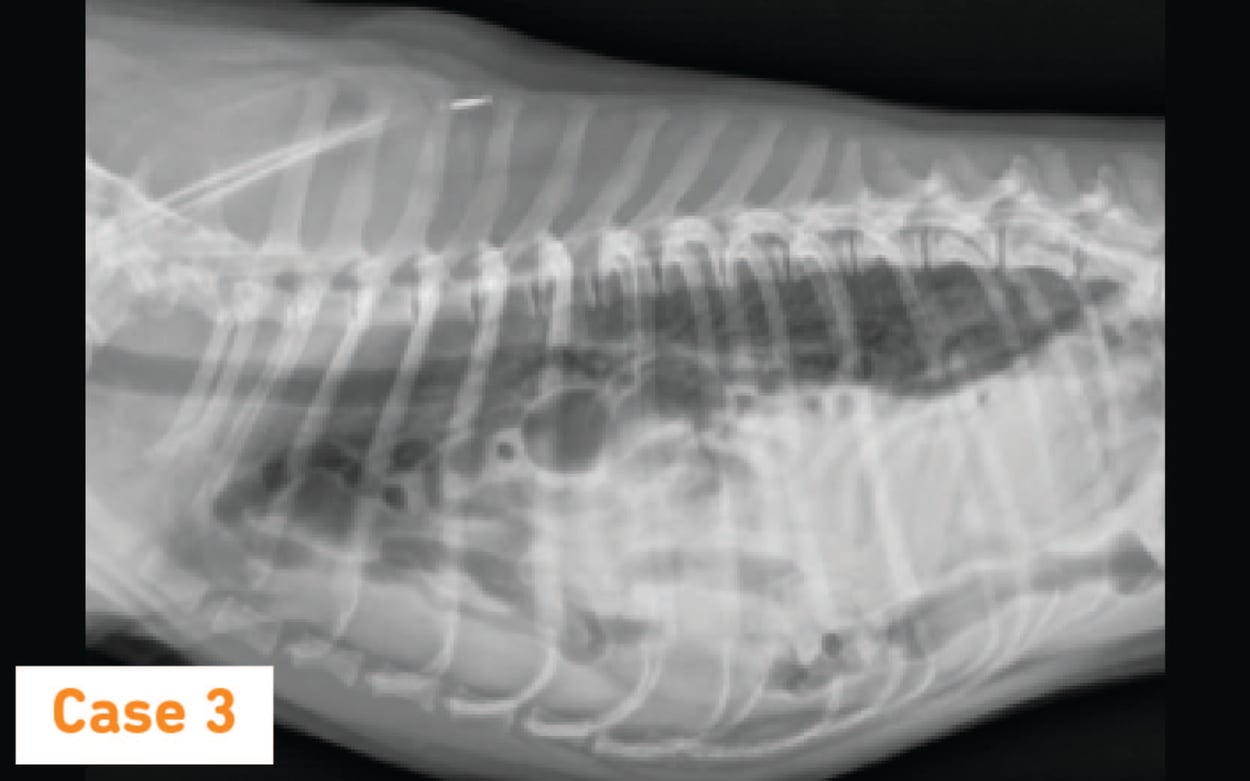

Cat X Ray. Diaphragmatic Hernia in Cat. Stock Image Image of anatomy How Long Can A Cat Live With Diaphragmatic Hernia A diaphragmatic hernia in cats is a tear or rupture in the diaphragm. A diaphragmatic hernia is a condition in which a break in the diaphragm allows protrusion of abdominal organs into the chest. As mentioned above, some cats may live for years with an undiagnosed diaphragmatic hernia, so yes, it is possible for cats to live with one. A. How Long Can A Cat Live With Diaphragmatic Hernia.

X Ray Diaphragmatic Hernia Cat Side Stock Photo 1253071330 Shutterstock How Long Can A Cat Live With Diaphragmatic Hernia A feline with a diaphragmatic hernia will be reluctant to exercise due to the. Dogs and cats with a mild diaphragmatic hernia can live with the condition for years without showing clinical signs. After a blow, fall or fight, internal damage can occur, including the rupture. A diaphragmatic hernia in cats is a tear or rupture in the diaphragm. As. How Long Can A Cat Live With Diaphragmatic Hernia.